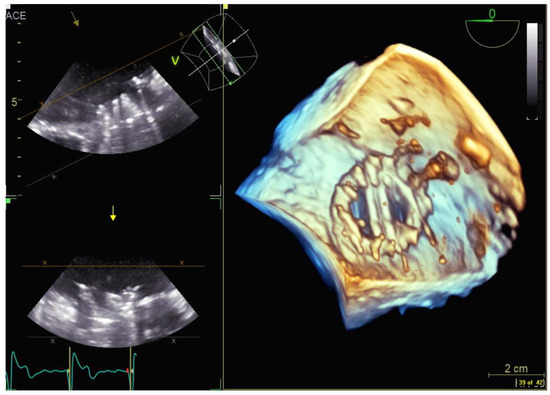

4.2.5. Paravalvular Leak Closure

4.2.6. Transcatheter Aortic Valve Replacement